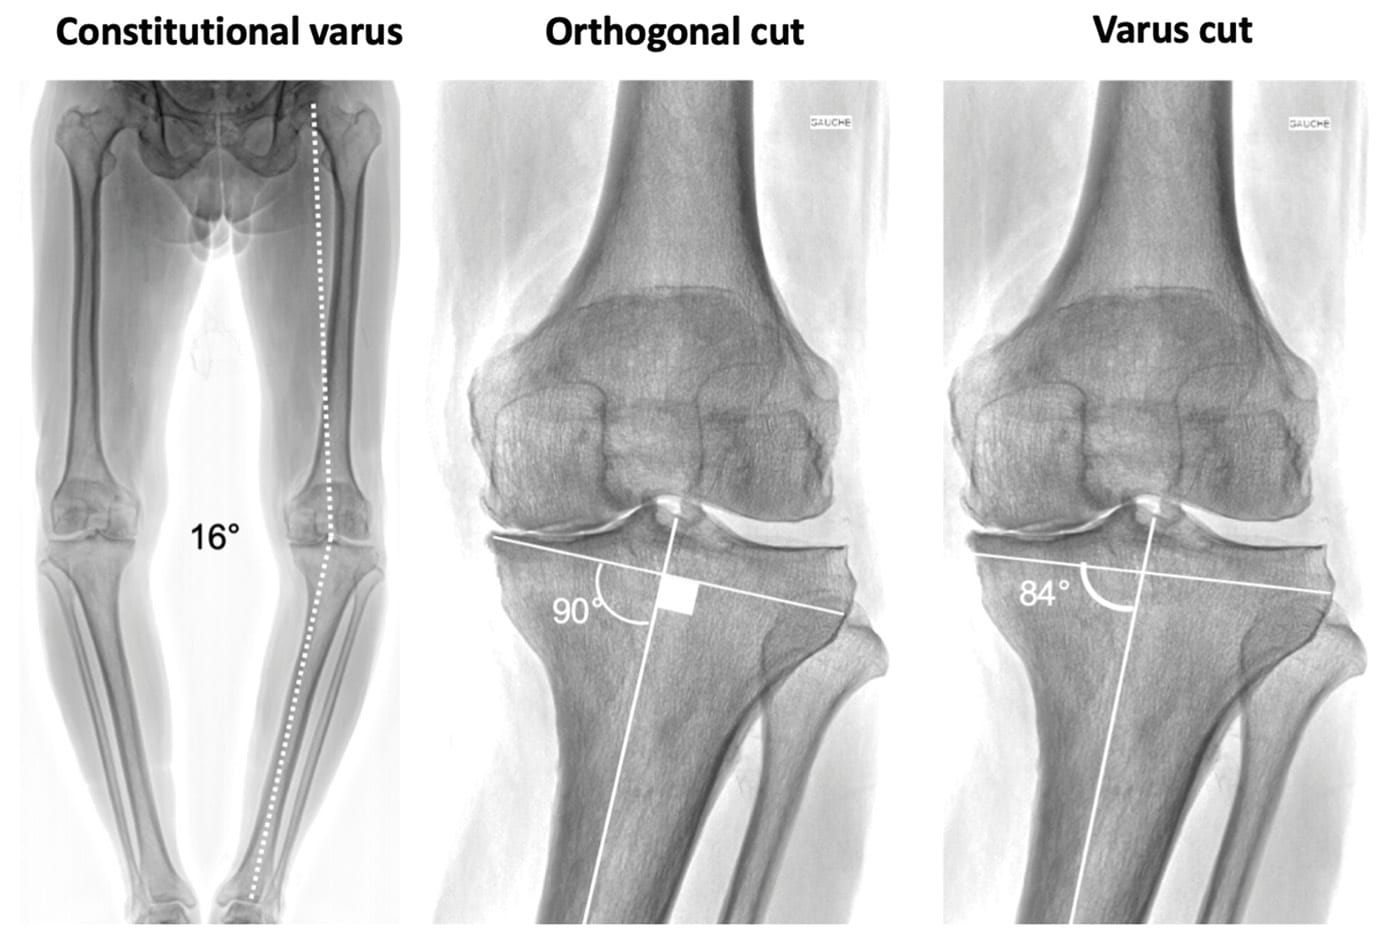

From pre-operative to pre-arthritic alignment: predicting the past

One of the main paradigm shifts of knee arthroplasty in the last decades has been the switch from systematic alignment (mechanical or anatomic) to individualized alignment (kinematic, restricted, inverse kinematic, or functional alignment…) [2], Beckers G, Meneghini RM, Hirschmann MT, Kostretzis L, Kiss MO, Vendittoli PA (2024) Ten Flaws of Systematic Mechanical Alignment Total Knee Arthroplasty. J Arthroplasty 39 (3):591-599. [24], Rivière C, Vigdorchik JM, Vendittoli PA (2019) Mechanical alignment: The end of an era! Orthop Traumatol Surg Res 105 (7):1223-1226. [27] Saffarini M, Hirschmann MT, Bonnin M (2023) Personalisation and customisation in total knee arthroplasty: the paradox of custom knee implants. Knee Surg Sports Traumatol Arthrosc 31 (4):1193-1195. . Many surgeons have abandoned the concept of ‘90° cuts for all’ and now try to restore, at least partially, the native phenotype (femoral and tibial angles as well as joint line orientation) [2], Beckers G, Meneghini RM, Hirschmann MT, Kostretzis L, Kiss MO, Vendittoli PA (2024) Ten Flaws of Systematic Mechanical Alignment Total Knee Arthroplasty. J Arthroplasty 39 (3):591-599. [3], Blakeney W, Beaulieu Y, Puliero B, Kiss MO, Vendittoli PA (2020) Bone resection for mechanically aligned total knee arthroplasty creates frequent gap modifications and imbalances. Knee Surg Sports Traumatol Arthrosc 28 (5):1532-1541. [4], Blakeney W, Clément J, Desmeules F, Hagemeister N, Rivière C, Vendittoli PA (2019) Kinematic alignment in total knee arthroplasty better reproduces normal gait than mechanical alignment. Knee Surg Sports Traumatol Arthrosc 27 (5):1410-1417. [15], Karasavvidis T, Pagan Moldenhauer CA, Haddad FS, Hirschmann MT, Pagnano MW, Vigdorchik JM (2023) Current Concepts in Alignment in Total Knee Arthroplasty. J Arthroplasty 38 (7 Suppl 2):S29-s37. [16], Karasavvidis T, Pagan Moldenhauer CA, Lustig S, Vigdorchik JM, Hirschmann MT (2023) Definitions and consequences of current alignment techniques and phenotypes in total knee arthroplasty (TKA) - there is no winner yet. J Exp Orthop 10 (1):120. [18], Lustig S, Sappey-Marinier E, Fary C, Servien E, Parratte S, Batailler C (2021) Personalized alignment in total knee arthroplasty: current concepts. [22], Rivière C, Iranpour F, Auvinet E, Howell S, Vendittoli PA, Cobb J, Parratte S (2017) Alignment options for total knee arthroplasty: A systematic review. Orthop Traumatol Surg Res 103 (7):1047-1056. [24] Rivière C, Vigdorchik JM, Vendittoli PA (2019) Mechanical alignment: The end of an era! Orthop Traumatol Surg Res 105 (7):1223-1226. . However, most surgeons plan their procedures on plain radiographs showing only the global deformity of the limb, which is a combination of native alignment, arthritic remodelling (bone wear and laxity), and radiologic errors due to fixed flexion deformity and/or malrotation[5] Bonnin MP, Beckers L, Leon A, Chauveau J, Müller JH, Tibesku CO, Aït-Si-Selmi T (2022) Custom total knee arthroplasty facilitates restoration of constitutional coronal alignment. Knee Surg Sports Traumatol Arthrosc 30 (2):464-475. . It is therefore unrealistic to deduce the true native alignment of a given patient from their preoperative radiograph. This is a main limitation because: (i) in daily life we only have an approximate knowledge of a patient’s phenotype and (ii) the literature never differentiates native and arthritic deformities and fails to define the appropriate targets (Figure 3).

An important advantage of 3D CT planning is that it enables direct visualization of the bone defects, which generally involve only a limited area of the tibial plateau (or more rarely the condyle), and to deduce the native shape of the articular surface by referring to non-damaged areas (Figure 4) [7] Dossett HG, Estrada NA, Swartz GJ, LeFevre GW, Kwasman BG (2014) A randomised controlled trial of kinematically and mechanically aligned total knee replacements: two-year clinical results. Bone Joint J 96-b (7):907-913. . While the femur and tibia are analyzed separately, it is possible to calculate the native femoral and tibial angles, the arithmetic HKA, and to know the precise native phenotype of the patient. All technologies based on preoperative CT analysis provide this advantage, and the success of image-based robotics is due to, among other reasons, this possibility to plan in 3D and to facilitate the kinematic alignment technique [1], Batailler C, Bordes M, Lording T, Nigues A, Servien E, Calliess T, Lustig S (2021) Improved sizing with image-based robotic-assisted system compared to image-free and conventional techniques in medial unicompartmental knee arthroplasty. Bone Joint J 103-b (4):610-618. [14], Huber K, Christen B, Calliess S, Calliess T (2021) True Kinematic Alignment Is Applicable in 44% of Patients Applying Restrictive Indication Criteria-A Retrospective Analysis of 111 TKA Using Robotic Assistance. J Pers Med 11 (7). [19] Morcos MW, Uhuebor D, Vendittoli PA (2023) Overview of the different personalized total knee arthroplasty with robotic assistance, how choosing? Front Surg 10:1120908. .